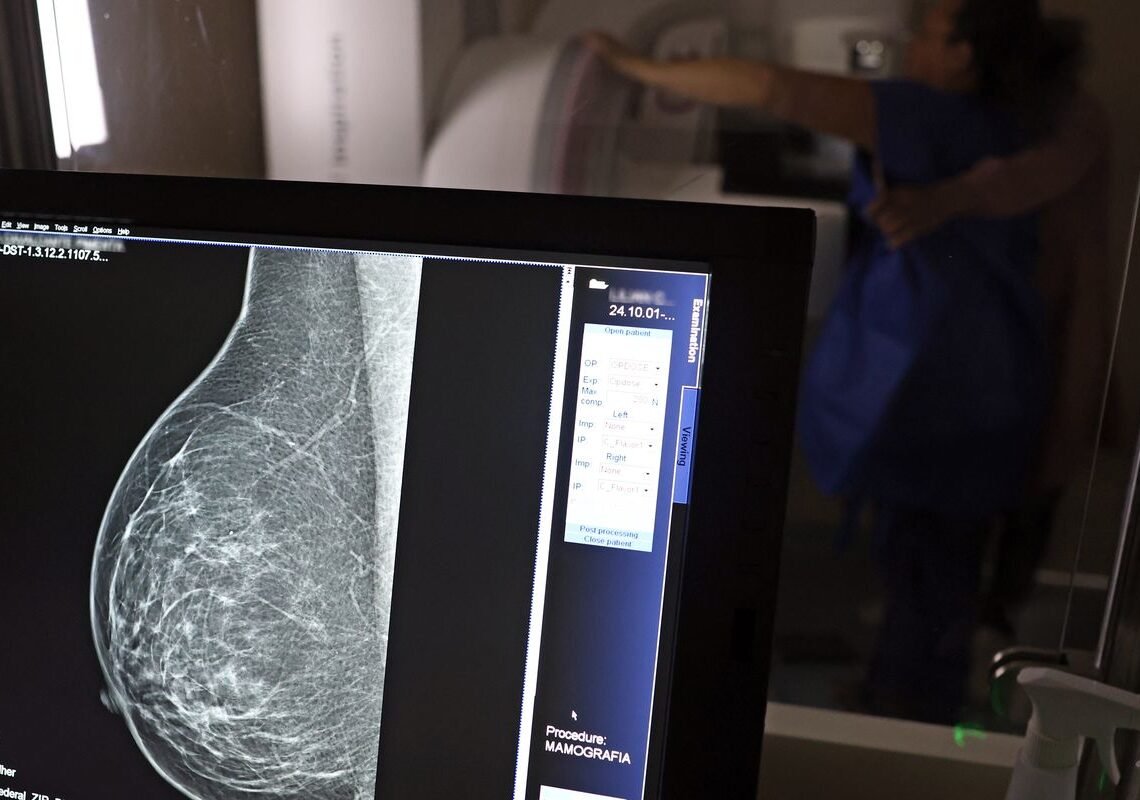

O Ministério da Saúde passou a recomendar o acesso a mamografia, via Sistema Único de Saúde (SUS), para mulheres de 40 a 49 anos – mesmo que não haja sinais ou sintomas de câncer de mama. De acordo com a pasta, a faixa etária concentra 23% dos casos da doença, e a detecção precoce aumenta as chances de cura.

Até então, a orientação era que o exame fosse feito a partir dos 50 anos.

A medida faz parte de um conjunto de ações anunciadas nesta terça-feira (23) voltado para a melhoria do diagnóstico e da assistência. A recomendação para mulheres a partir dos 40 anos é que o exame seja feito sob demanda, em decisão conjunta com o profissional de saúde.

As mamografias via SUS em pacientes com menos de 50 anos, de acordo com a pasta, representam 30% do total, o equivalente a mais de 1 milhão apenas no ano de 2024.

Outra medida anunciada é a ampliação da faixa etária para o rastreamento ativo – quando a mamografia é solicitada de forma preventiva a cada dois anos. A idade limite, até então, era 69 anos. Agora, passa a ser 74 anos. Dados do ministério revelam que quase 60% dos casos de câncer de mama estão concentrados entre 50 e 74 anos.

Os números mostram que, em 2024, cerca de 4 milhões de mamografias para rastreamento e 376,7 mil exames diagnósticos foram realizados no SUS.